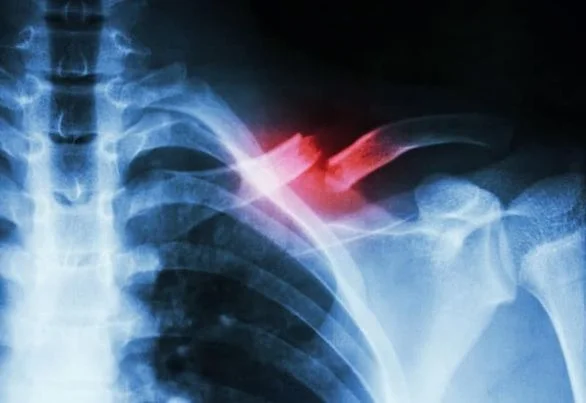

GÃY XƯƠNG ĐÒN VÀ NHỮNG CÁCH ĐIỀU TRỊ HIỆU QUẢ

1. Triệu chứng Xương đòn nằm ở vị trí giữa lồng ngực và phần bả vai nối với cánh tay. Khi xương đòn vai bị gãy, người bệnh sẽ gặp phải một số triệu chứng...